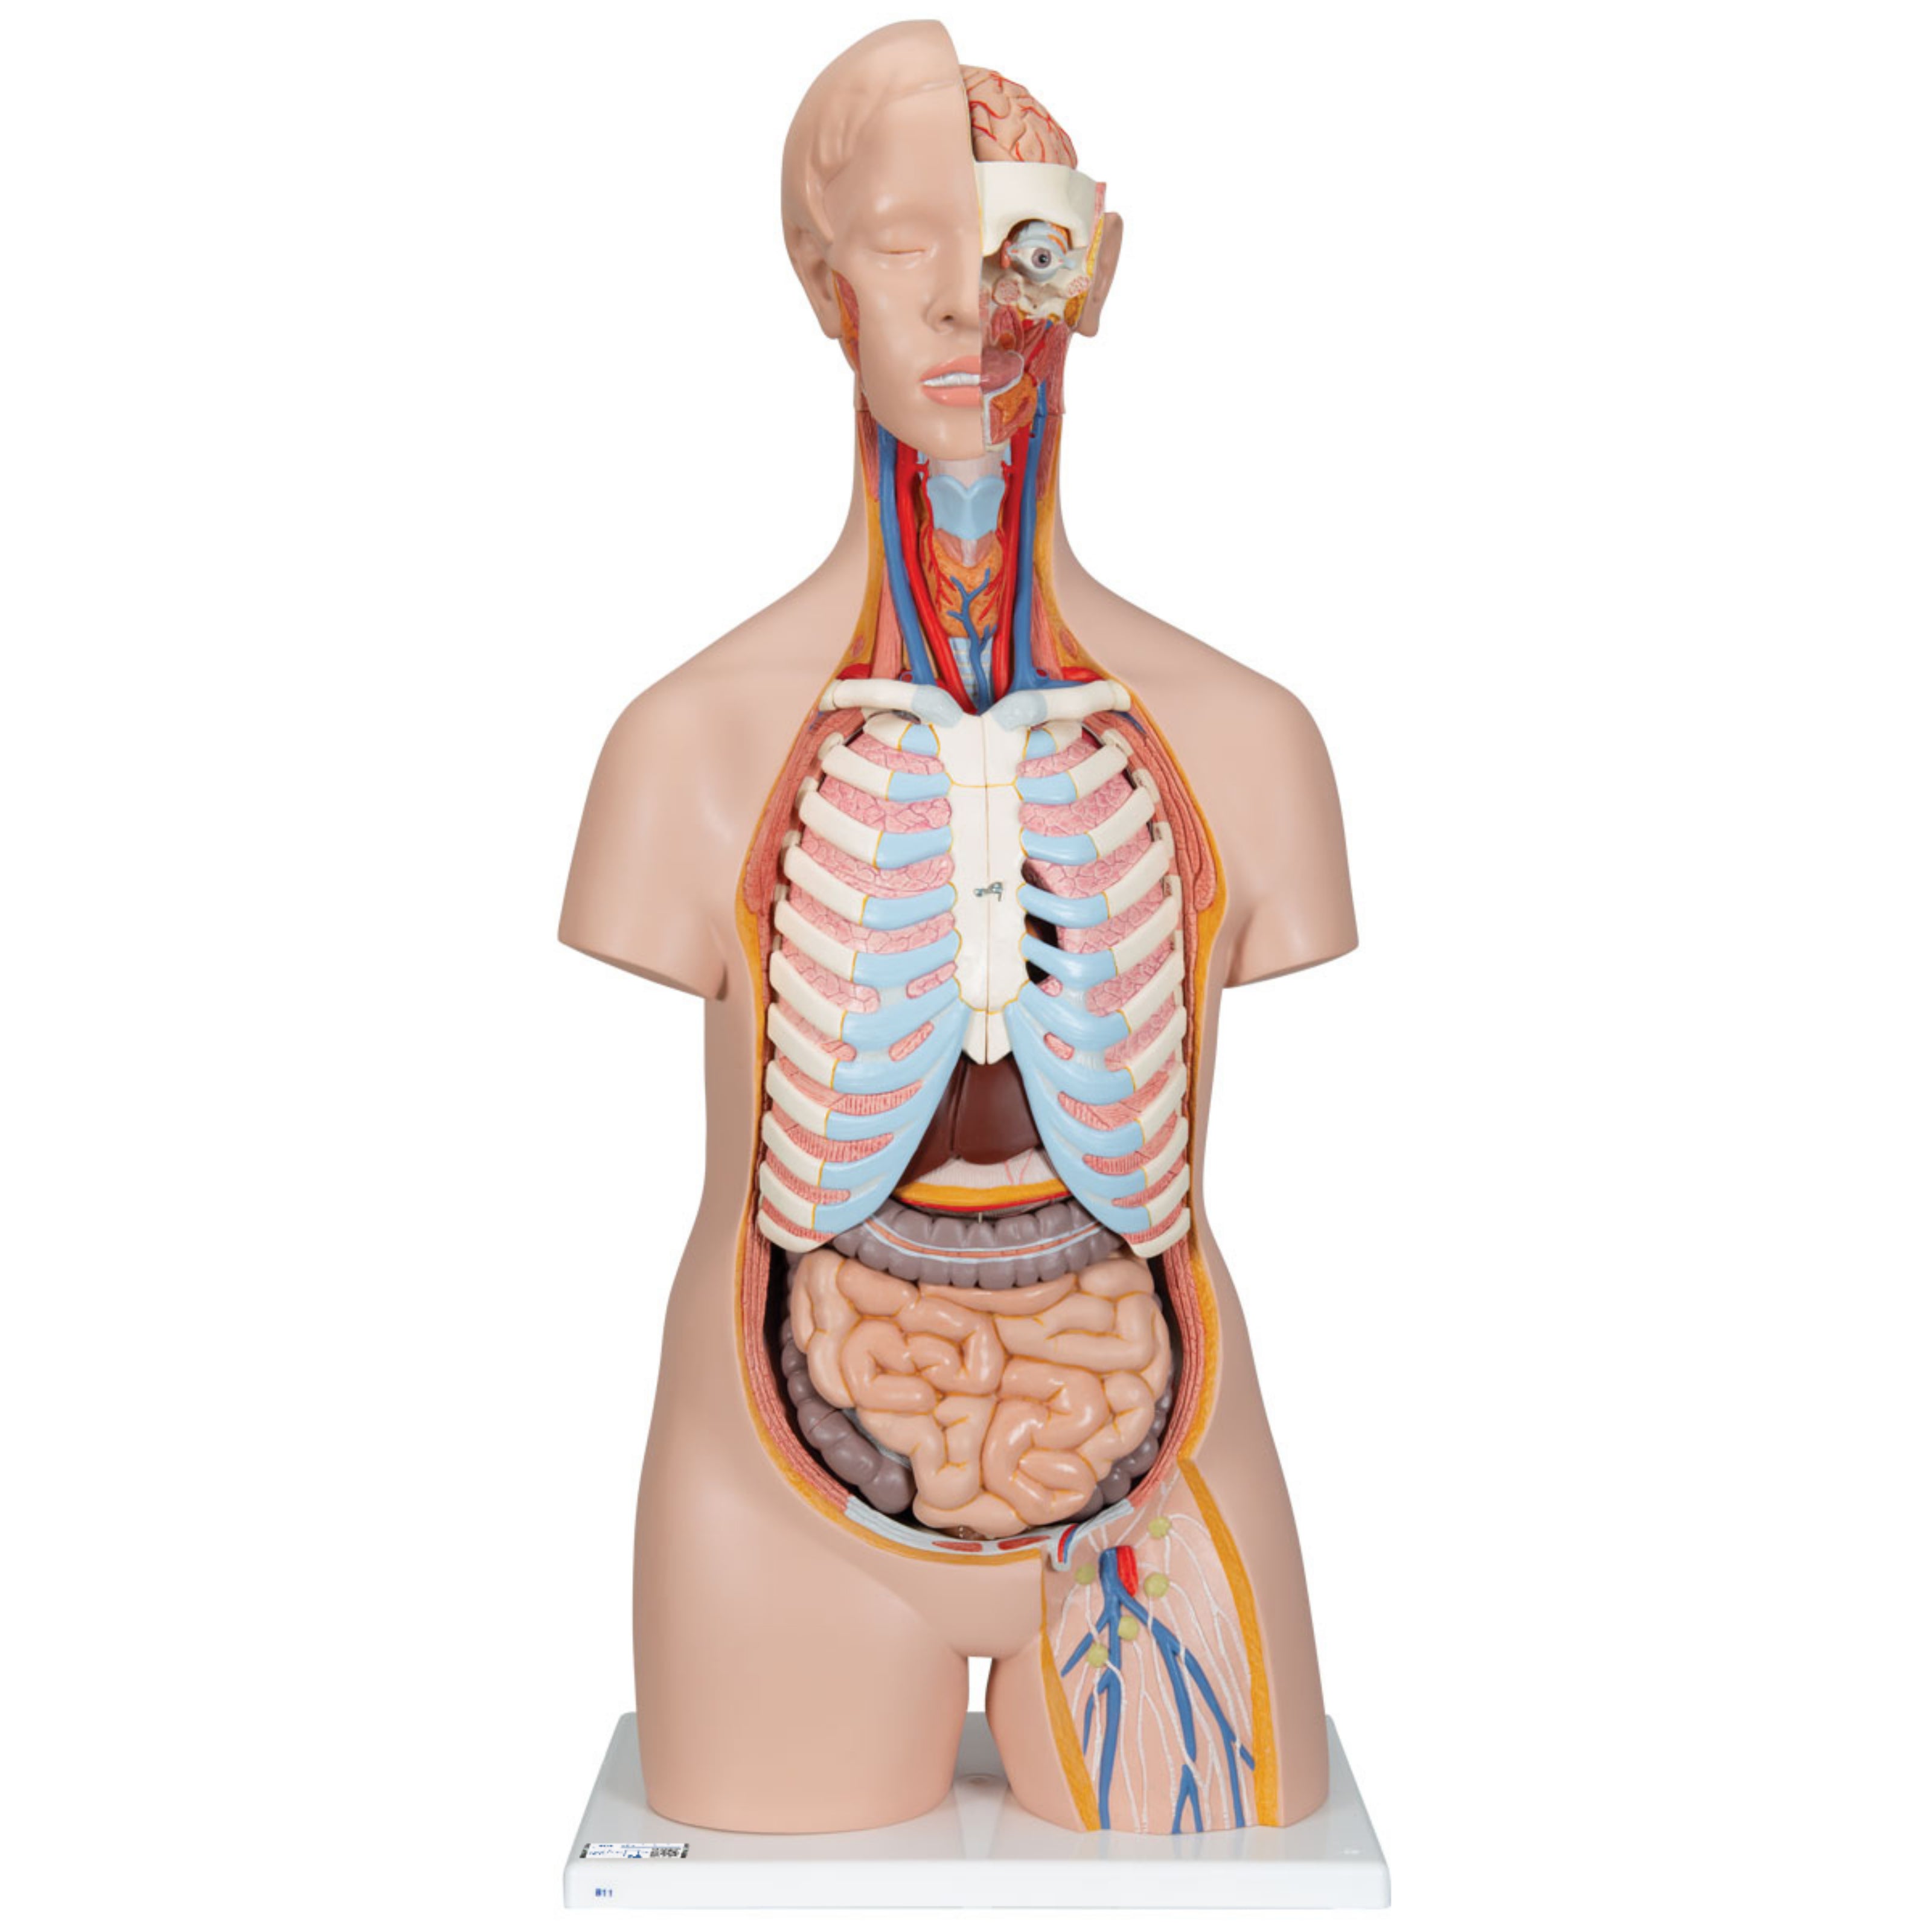

Torso clásico con espalda abierta, 18 partes - 3B Smart Anatomy

Precio de venta$33,762.96